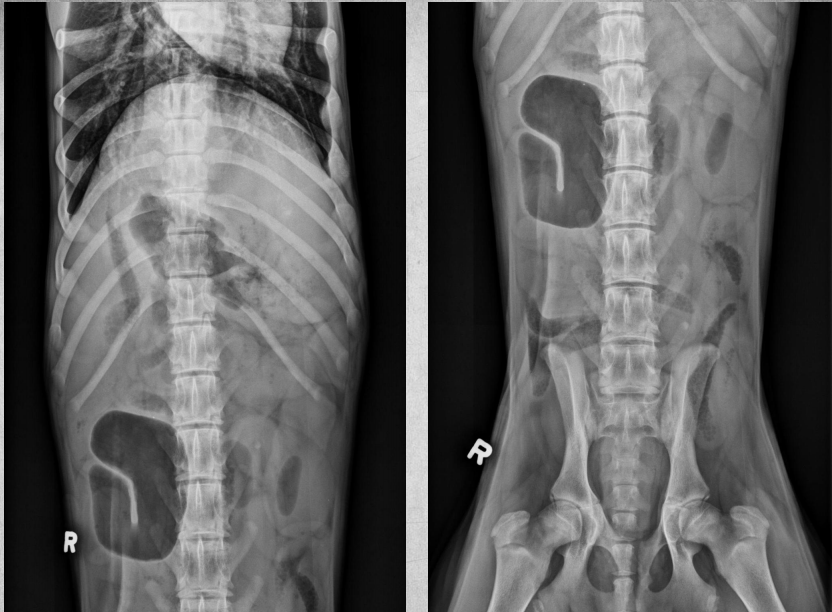

●6 yo castrated male Ragdoll

●Very thin

●Vomiting

● Liver mildly enlarged, rounded with mass effect.

● Kidneys markedly increased in size,

irregularly shaped, displaced ventrally

● Severe bilateral polycystic kidney disease

● Concurrent polycystic liver disease

soft tissue and fluid have the same density so the cysts are all homogenous with the renal tissue. you’d see the cyst pockets on ultrasound.